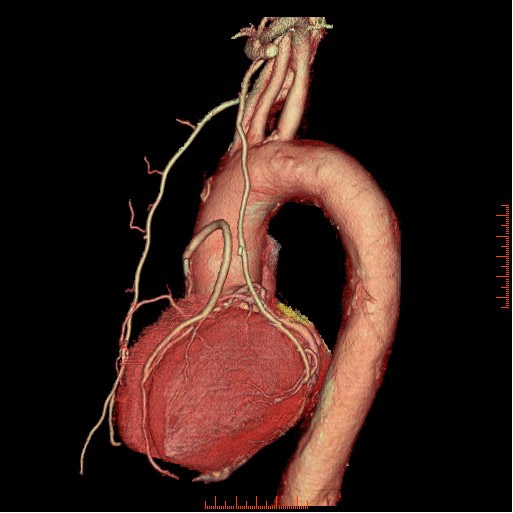

冠状動脈バイパス手術後の経過観

手術後の患者様の経過を下記の通り観察できます。心臓の裏側ももちろん診断可能です。

様々な画像表示処理方法を用い診断します。

ボリュームレンダリング